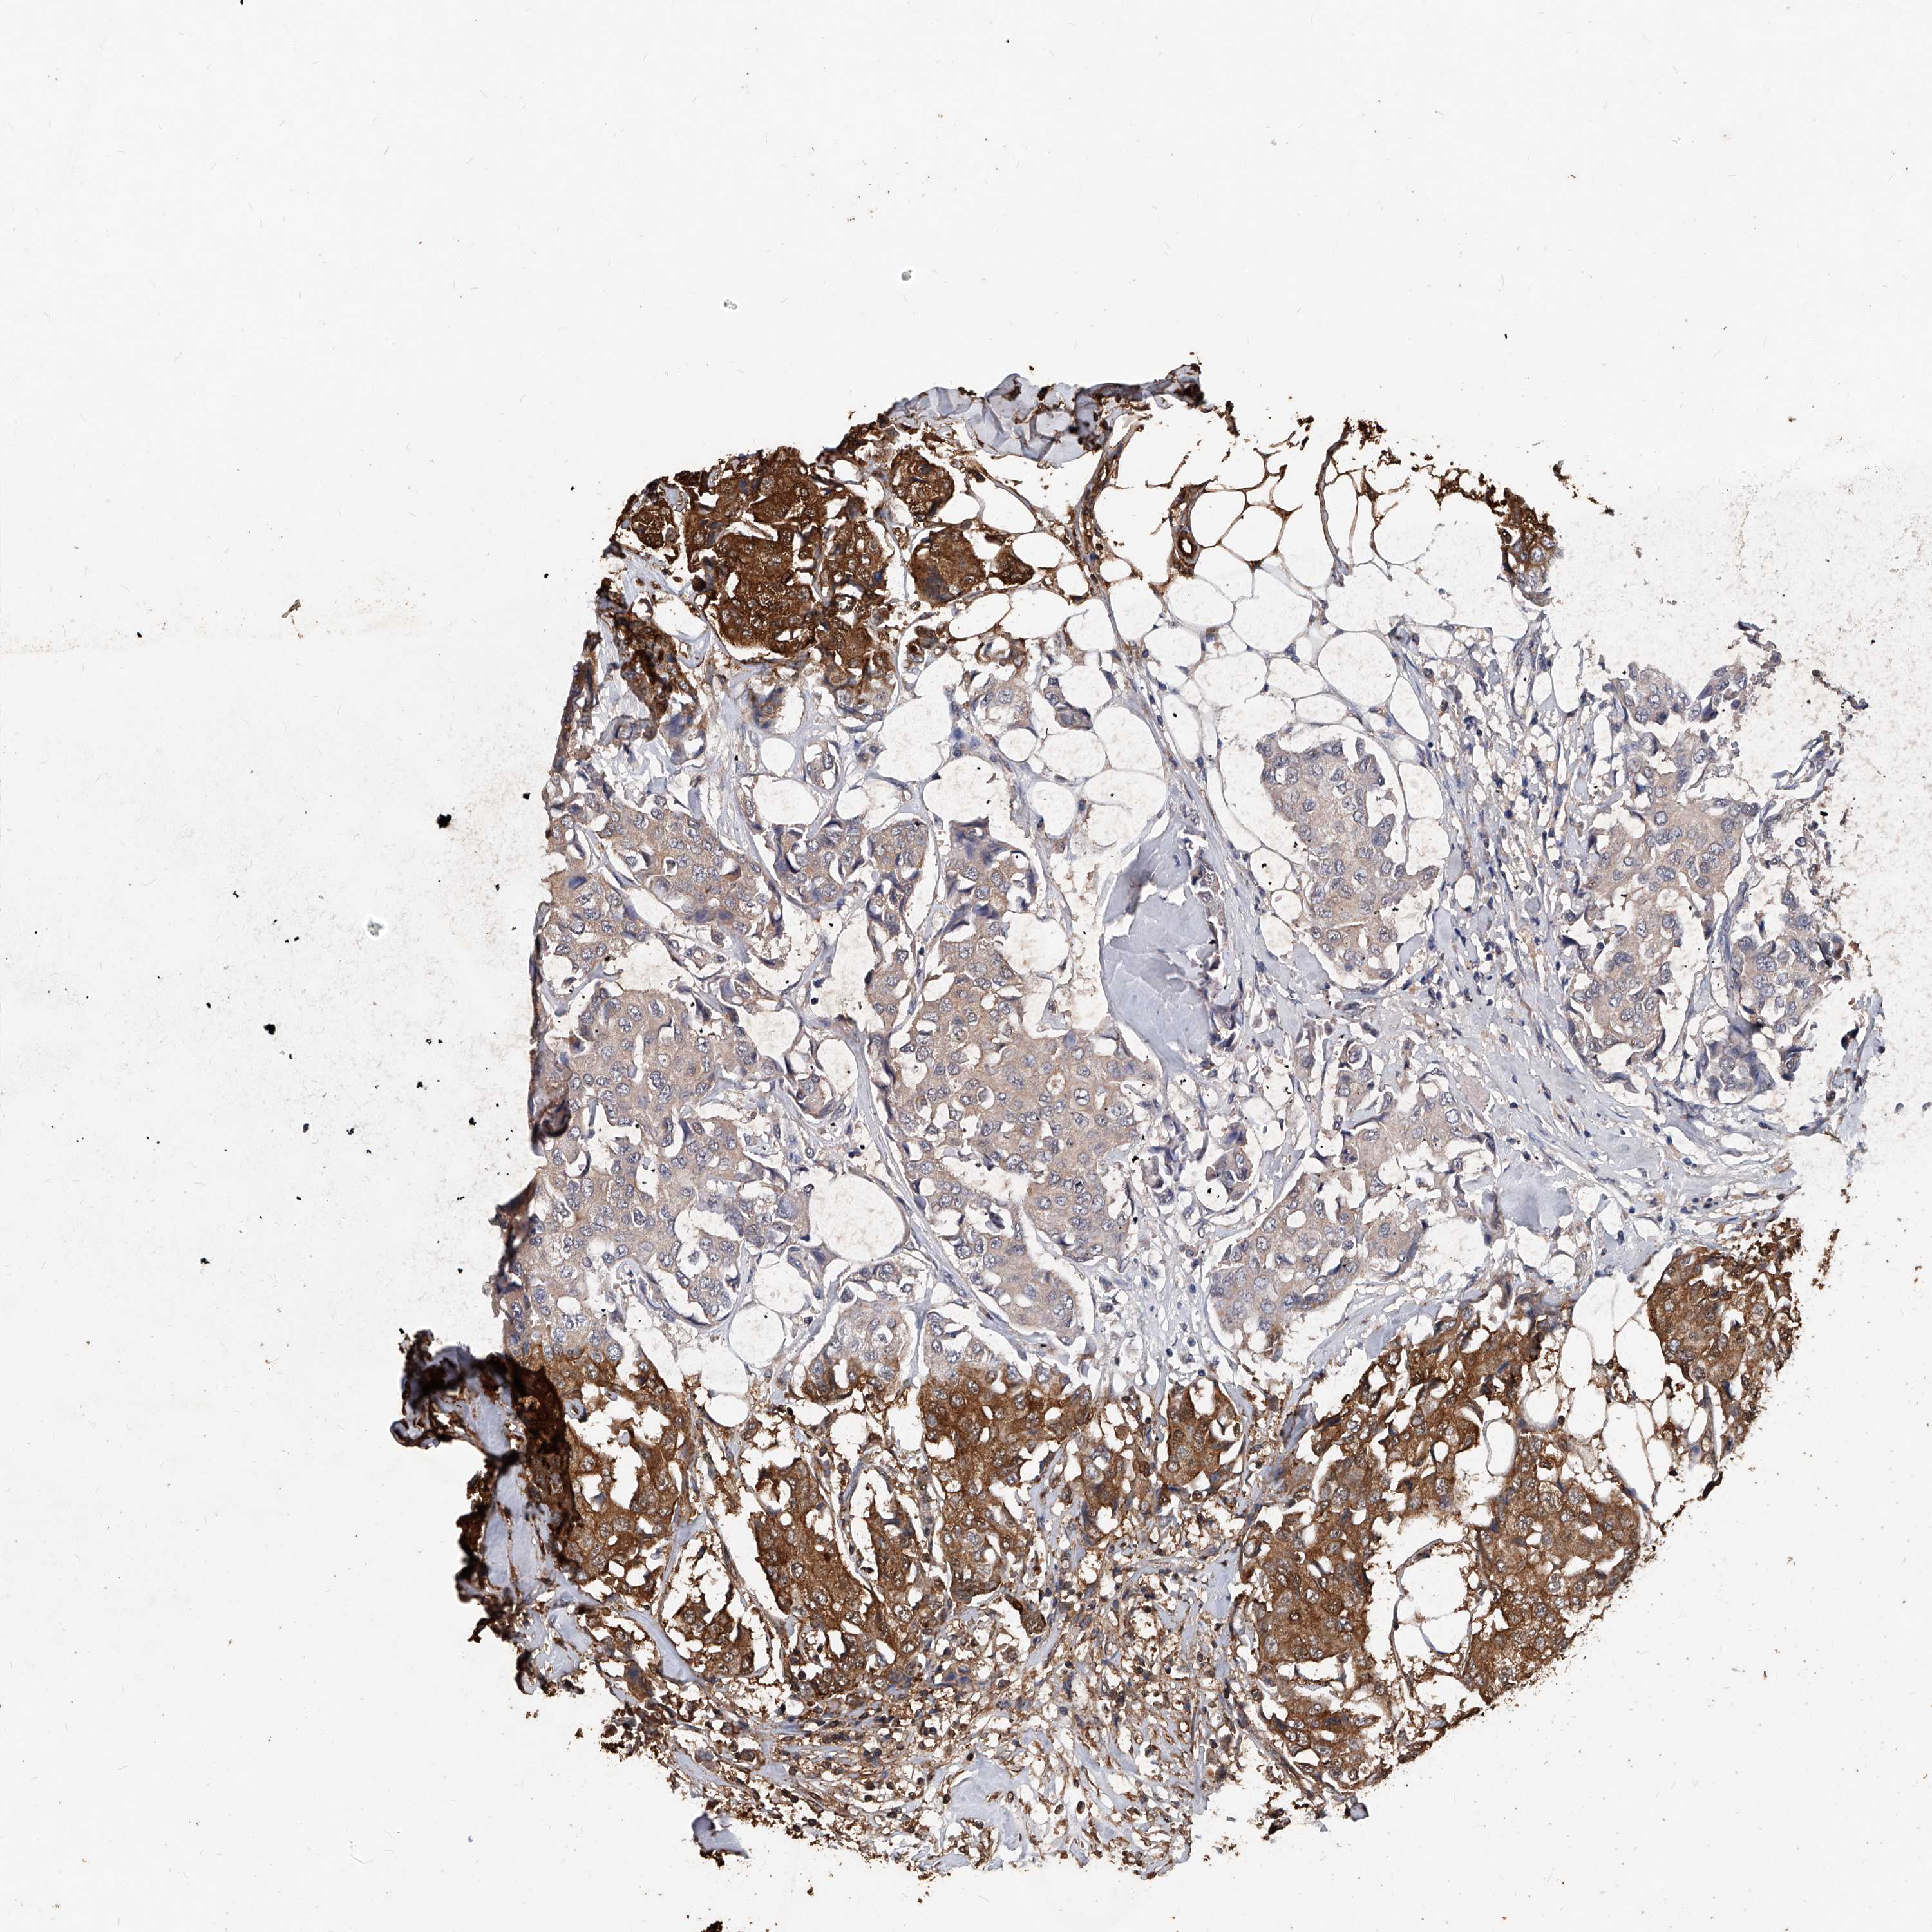

CANCER BREAST CANCER Show tissue menu

BRCA TCGA BRCA VALIDATION PROTEIN EXPRESSION

Breast cancer

Human cancer